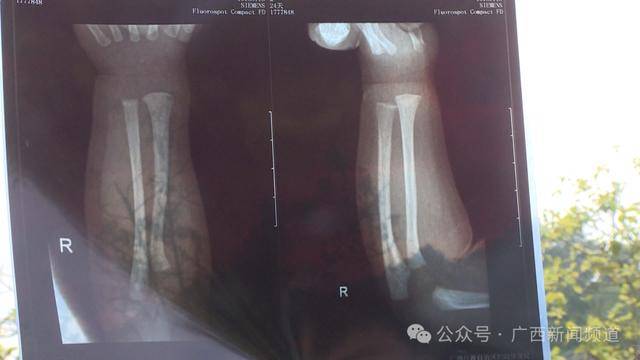

经过医生诊断,发现宝宝右手有两处骨折,第一处为右侧尺骨远端骨折,第二处为右侧桡骨远端骨折皇冠信用网代理。医生给宝宝受伤的手臂做了石膏固定。回到月子中心后没过几天,意外又发生了。